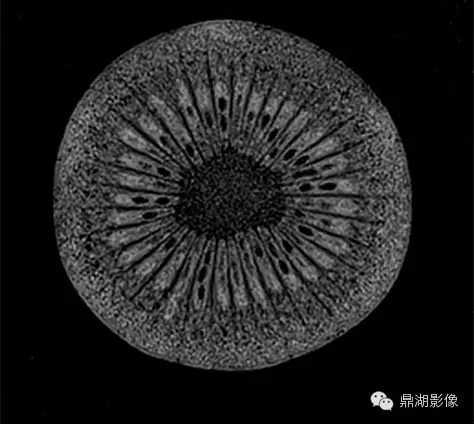

7T磁共振下的猕猴桃